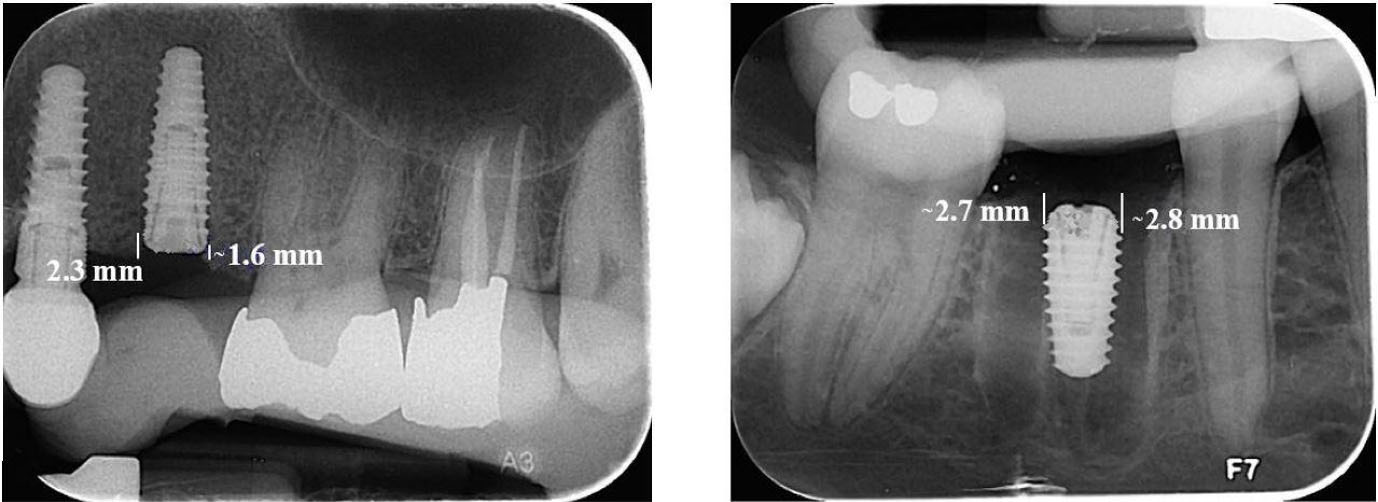

The intraoral images were analyzed using Scanora software, version 5.2.6. Measurements were taken from both mesial and distal sides of the fixture from the first implant thread to the highest point of crestal bone to assess the alveolar crest level. The measurement from the first radiograph was considered a reference for bone crest height; radiographs taken at two and four months were compared to this reference (Figure 2).

Figure 2.

Measuring the height of the crestal bone in the Scanore software